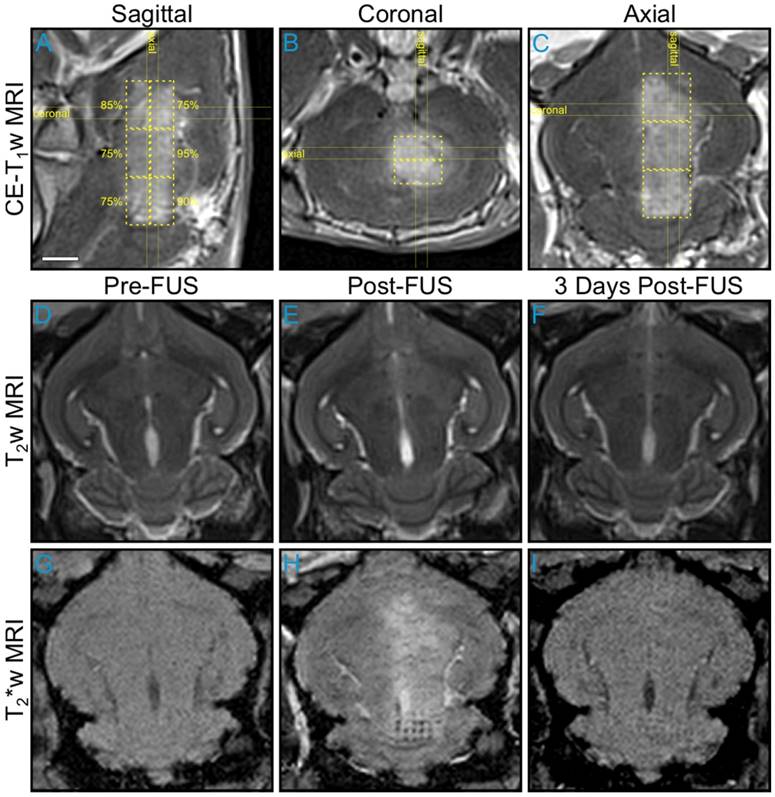

An example of large volume BBB opening in an animal from the pilot group is shown in Figure 5. Six non-overlapping multi-point grids (6 × 6 points per grid, 1.0 mm spacing) were sonicated at target levels ranging from 75-95%. Increased levels of BBB permeability (relative to the unsonicated contralateral tissue) were induced within each targeted region, and the resulting volume of opening was assessed via CE-T1w MRI to be approximately 850 mm3 (Figure 5A-C). No obvious regions of signal hyperintensity induced by the sonications were visible on T2w MRI scans acquired both immediately post-sonication (Figure 5D-E) and prior to animal sacrifice 3 days post-FUS (Figure 5F). Regions of signal hypointensity that were not present pre-treatment can be seen on corresponding T2*w MRI scans acquired immediately post-sonication, particularly in the posterior-most target volume where a clear grid pattern is apparent within a subset of the treated region (Figure 5G-H). Follow-up MRI scans taken 3 days post-FUS indicated that the T2*w hypointensities had been reduced in number and were less apparent at this time in terms of levels of signal intensity reduction relative to unsonicated tissue (Figure 5I). Histological examination in this animal confirmed the presence of extravasated RBCs in the sonicated hemisphere at the 3 day time point, including regions that were exposed at the 75% target level (data not shown).

Figure 5

Multi-point exposures enable large volume BBB opening. Example of large volume ultrasound-mediated BBB opening and tissue damage in an animal from the pilot group, assessed via MRI. Six non-overlapping grids (6 × 6, 1.0 mm point spacing) were sonicated at target levels ranging from 75-95%. (A) Sagittal, (B) coronal, and (C) axial CE-T1w MR images depicting increased BBB permeability within each targeted volume (yellow dashed regions, total volume ≈ 850 mm3). The target levels for each grid are labeled in (A). The horizontal and vertical yellow lines in (A-C) indicate the imaging slice volumes for the two orthogonal planes. The CE-T1w MR images were acquired immediately following sonication of the sixth multi-point grid. Four MRI contrast agent injections (4 × 0.1 mL/kg) had been administered in this animal over the course of 90 min at the time of image acquisition. Axial T2w MR images acquired (D) pre-, (E) 20 min post-, and (F) 3 days post-FUS. No obvious regions of T2w MRI signal hyperintensity induced by the exposures were present in this animal. Axial T2*w MR images acquired (G) pre-, (H) 15 min post-, and (I) 3 days post-FUS. Regions of T2*w MRI signal hypointensity induced by the exposures are apparent, particularly in the posterior-most grid (H-I), which was sonicated at the 90% target level. The sonication direction is out of the page, bottom-to-top, and right-to-left when viewing axial, coronal, and sagittal MR images, respectively. Scale bar indicates 5 mm.